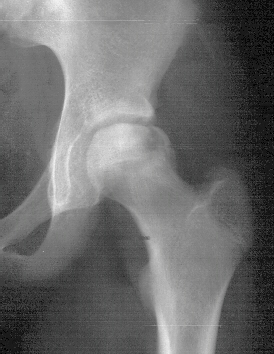

The

concern about avascular necrosis of the hip at this age with a

cold bone scan suggests that she should be placed on crutches

until a clear documentation of the severity of the bone involvement

can be ascertained.